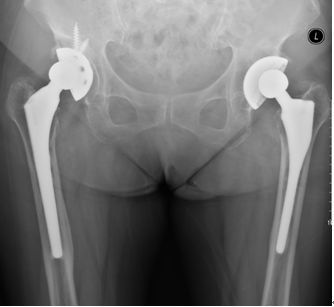

78岁,女性患者,1997年、1998年分别于外院行左侧、右侧全髋关节置换术,术后无痛,功能恢复良好;2011年开始出现右髋疼痛,外院保守治疗,症状缓解不明显,2012年始无法行走,需轮椅代步,来诊X片如上。

2012年5月于我院行右侧髋关节翻修术,2019年右髋翻修术后近7年,左侧初次置换术后22年,2019年1月复查照片,双髋关节假体稳定,位置角度可,患者生活可自理。